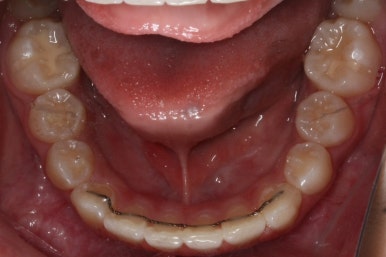

윗니만 6개월이 지난 모습입니다.

치열이 매우 가지런해졌죠. 이 후에는 특이사항 없이 종료가 되었습니다.

연산동덧니교정을 하고자 키다리아저씨치과에 처음 내원했을 때와 개선이 된 후의 비교 모습입니다. 영구치가 모두 나왔고 덧니가 개선이 된 후에 마무리가 되었습니다.